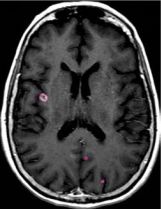

一位77岁的女性患有EPS15-NTRK1 IV期非小细胞肺癌,我们可以看到她的双肺满是病灶,并且出现了肝脏和脑转移,可以说是非常非常晚期了,

肺靶病变达到缓解,我们可以明显的看到前后的图像,病灶明显缩小了,

脑转移病变显示缩小了95%!

初始, 2018年6月             3周期 2018年8月